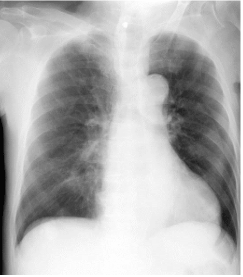

Anesthesia was induced with propofol, fentanyl, and rocuronium. However, tracheal intubation was difficult, and was performed with the intubating laryngeal mask airway. After intubation, careful inspection of the mouth confirmed that no teeth had been damaged. Anesthesia was maintained with sevoflurane, fentany [1], and remifentanil. The surgery was successfully completed, and the trachea was extubated. The anesthesiologist then suctioned the oral cavity; however, one tooth was dislodged during suctioning. Despite several attempts to grasp the tooth with a pair of forceps, the tooth disappeared into the throat. Bronchoscopy revealed that the tooth was neither in the trachea nor in the bronchus. A chest radiograph and computed tomography image showed that the tooth was in the esophagus, at the level of the first rib (Figure 1). We believed that the tooth would naturally move distally and be discharged from the digestive tract. However, a chest radiograph obtained the next day revealed that the tooth remained at the same location. Endoscopic examination of the esophagus did not detect the tooth at the most likely location indicated by the chest radiograph, and only normal-looking mucosa was observed. Following endoscopic examination, a chest radiograph was obtained after gas insufflation into the esophagus, and no mediastinal gas was noted. Therefore, it was unlikely that the tooth perforated the esophagus and migrated into the mediastinum. Endoscopy was then performed under fluoroscopic guidance to thoroughly examine the esophagus. The tip of the endoscope was positioned as close as possible to the tooth under fluoroscopic guidance, and a transparent plastic tube was used to push the esophageal mucosa at this site. The tooth was then squeezed out from the esophageal wall and was successfully removed. A pouch was identified, and it was diagnosed as a ZD (Figures 2 and 3).

Figure 1. A chest radiograph.